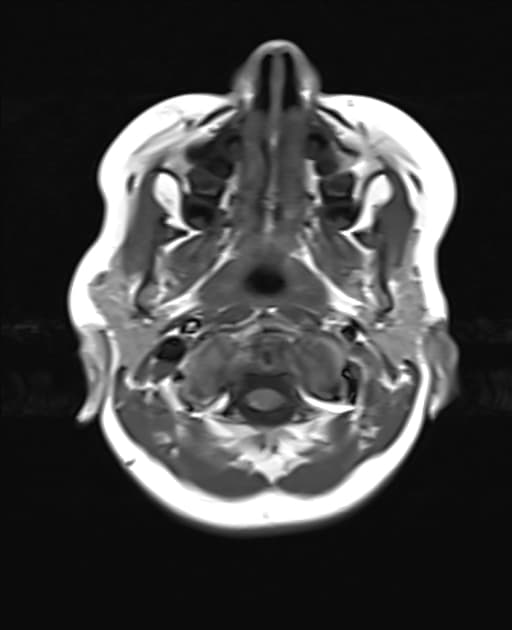

Temporal bone rhabdomyosarcoma with leptomeningeal metastases

Có một khối u dạng thùy, tăng quang không đồng nhất, khu trú tại ống tai ngoài, hòm nhĩ, các tế bào chũm và tai trong bên trái. Khối u có tín hiệu thấp trên các hình ảnh T1 và tín hiệu cao trên các chuỗi T2 và FLAIR. Đã ghi nhận sự xâm lấn vào góc cầu tiểu não bên trái. Có hiệu ứng khối đi kèm gây chèn ép lên não giữa, cầu não và não thất tư.

Phía trước, khối u tiếp giáp với thùy thái dương dưới. Sự xâm lấn vào phía trong dẫn đến tiếp giáp với khoang động mạch cảnh bên trái, với các khoảng trống tín hiệu dòng chảy vẫn được bảo tồn trong các mạch máu lân cận. Xâm lấn ra phía trước ngoài liên quan đến tuyến mang tai kèm theo một hạch bạch huyết tuyến mang tai lớn. Có tăng quang màng não dạng nốt dày dọc theo lều tiểu não bên trái, thân não, màng não vùng nền, vòm sọ và bán cầu tiểu não, phù hợp với lan tỏa màng não mềm.

Các khối u cạnh màng não có nguy cơ xâm lấn nội sọ và lan tỏa màng não mềm cao hơn, như đã thấy trong trường hợp này. Hình thái dạng thùy, tăng quang không đồng nhất, bao quanh mạch máu nhưng vẫn bảo tồn khoảng trống tín hiệu dòng chảy, lan truyền quanh dây thần kinh và nền sọ, liên quan hạch vùng và tăng quang màng não dạng nốt lan tỏa là những đặc điểm của bệnh giai đoạn muộn. Sự xâm lấn nội sọ vào góc cầu tiểu não và các cấu trúc hố sau, cùng với hiệu ứng khối lên thân não và não thất tư, phản ánh tính chất xâm lấn mạnh. Di căn màng não mềm ảnh hưởng đáng kể đến việc phân giai đoạn và tiên lượng, đồng thời đòi hỏi chẩn đoán hình ảnh toàn bộ trục thần kinh và quản lý ung thư đa chuyên khoa.